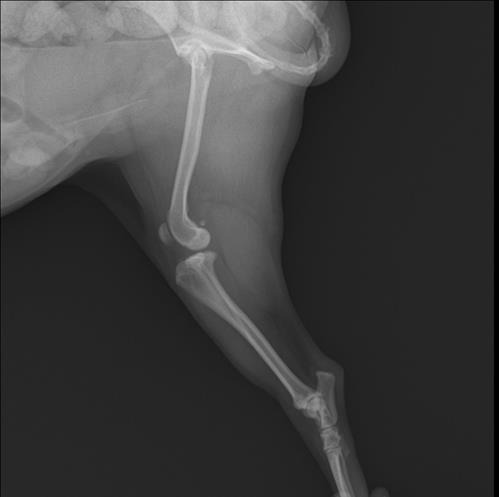

2016년생 10세 8kg 비숑입니다

오른쪽 뒷다리를 서있을째 떨다가 이젠 깽깽이발을 하길래 근처 동물병원을 갔더니 십자인대가 손상됐다고 했어요 파열이 아니라 체중감량하고 약물 처방 해줬다는데 진통제라 치료의 개념은 아니라고 생각하는데 근본적인 치료는 수술이 맞을까요..?